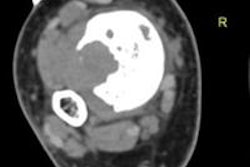

Researchers from Egypt have reported a high diagnostic performance of initial CT-guided percutaneous needle biopsy in extremity long bone lesions, particularly in the settings of malignant, mixed, and/or sclerotic lesions, as well as extraosseous exophytic tissue growth. Click here to find out more.